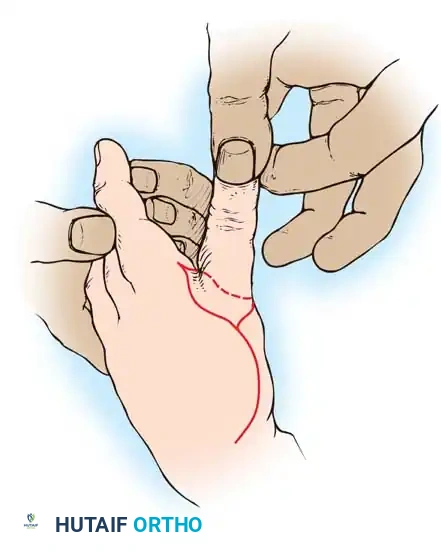

Amputation stumps that are painful due to thin skin coverage at the pulp and nail junction can be significantly improved by utilizing a limited volar advancement flap, classically described by Moberg.

* Design: The flap is outlined over the volar aspect of the digit, incorporating both neurovascular bundles to ensure robust perfusion and preserved sensibility.

* Elevation: The flap is raised deep to the neurovascular bundles, separating them from the flexor tendon sheath.

* Advancement: The flap is advanced distally (typically up to 1.5 cm) to cover the terminal defect.

* Limitations: In the fingers (unlike the thumb), proximal dissection to develop these flaps should not extend proximal to the proximal interphalangeal (PIP) joint. Extending beyond this point risks devascularization and severe flexion contractures.